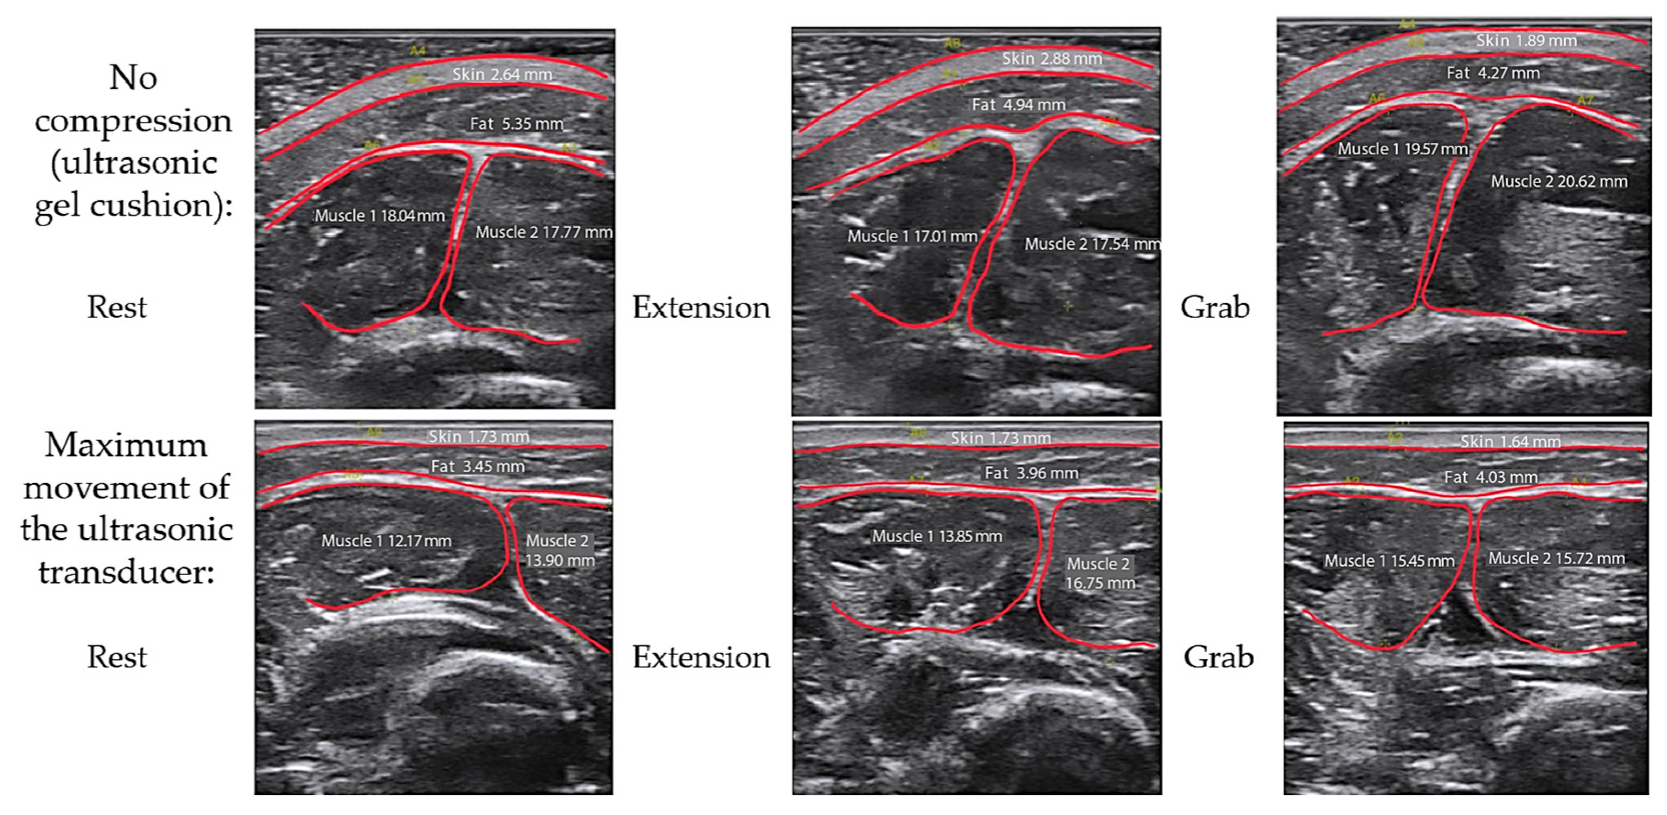

3.2. Study of the Amplitude Parameters of the Electrical Impedance Myography Signal at Different Pressures of the Electrode System